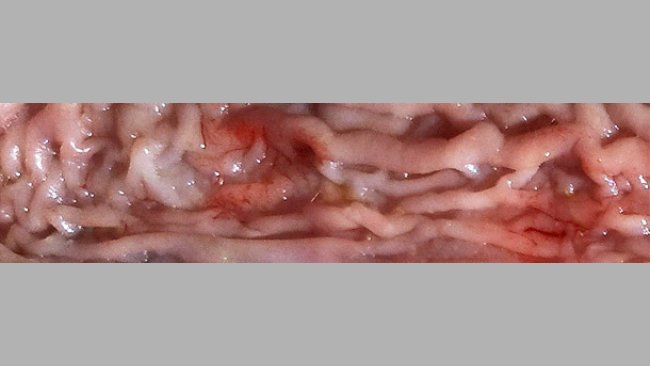

Descrição fotográfica das lesões mais significativas dos suínos

Por vezes é difícil fazer um diagnóstico adequado devido às co-infecções, os efeitos combinados de ambiente e nutrição e as dificuldades em identificar todos os possíveis agentes patogénicos implicados.

A ileite tem distintas formas de apresentação, inclusive na mesma exploração de engorda, e é frequente que coincida a forma subclínica com uma apresentação mais aguda e grave.